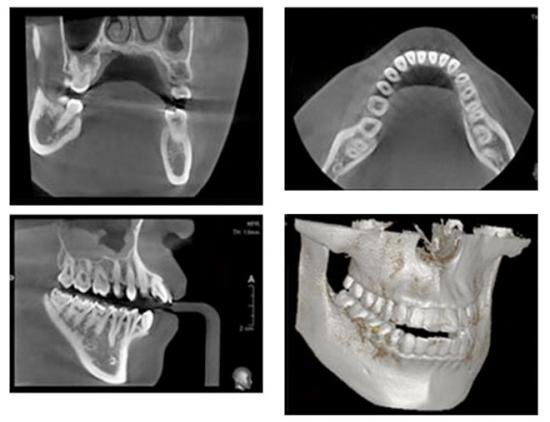

2検査と治療計画

インプラント治療が可能かどうか、歯科用CTを用いて顎の骨の密度や量の検査を行います。検査結果をもとに治療計画をご提案いたします。

顎の骨の密度や量の検査を行います。歯の型取りや、むし歯や歯周病のチェック、レントゲンや歯科用CTの撮影をします。

歯科用CT

歯科用CTにより精密な診査・診断を行うことができます。平面的なレントゲン画像だけでは分からない、顎の骨量や血管、神経の位置などを確認します。

親知らずの抜歯や、歯の根の治療、インプラントなどの精密な検査・処置が求められる治療には欠かせません。